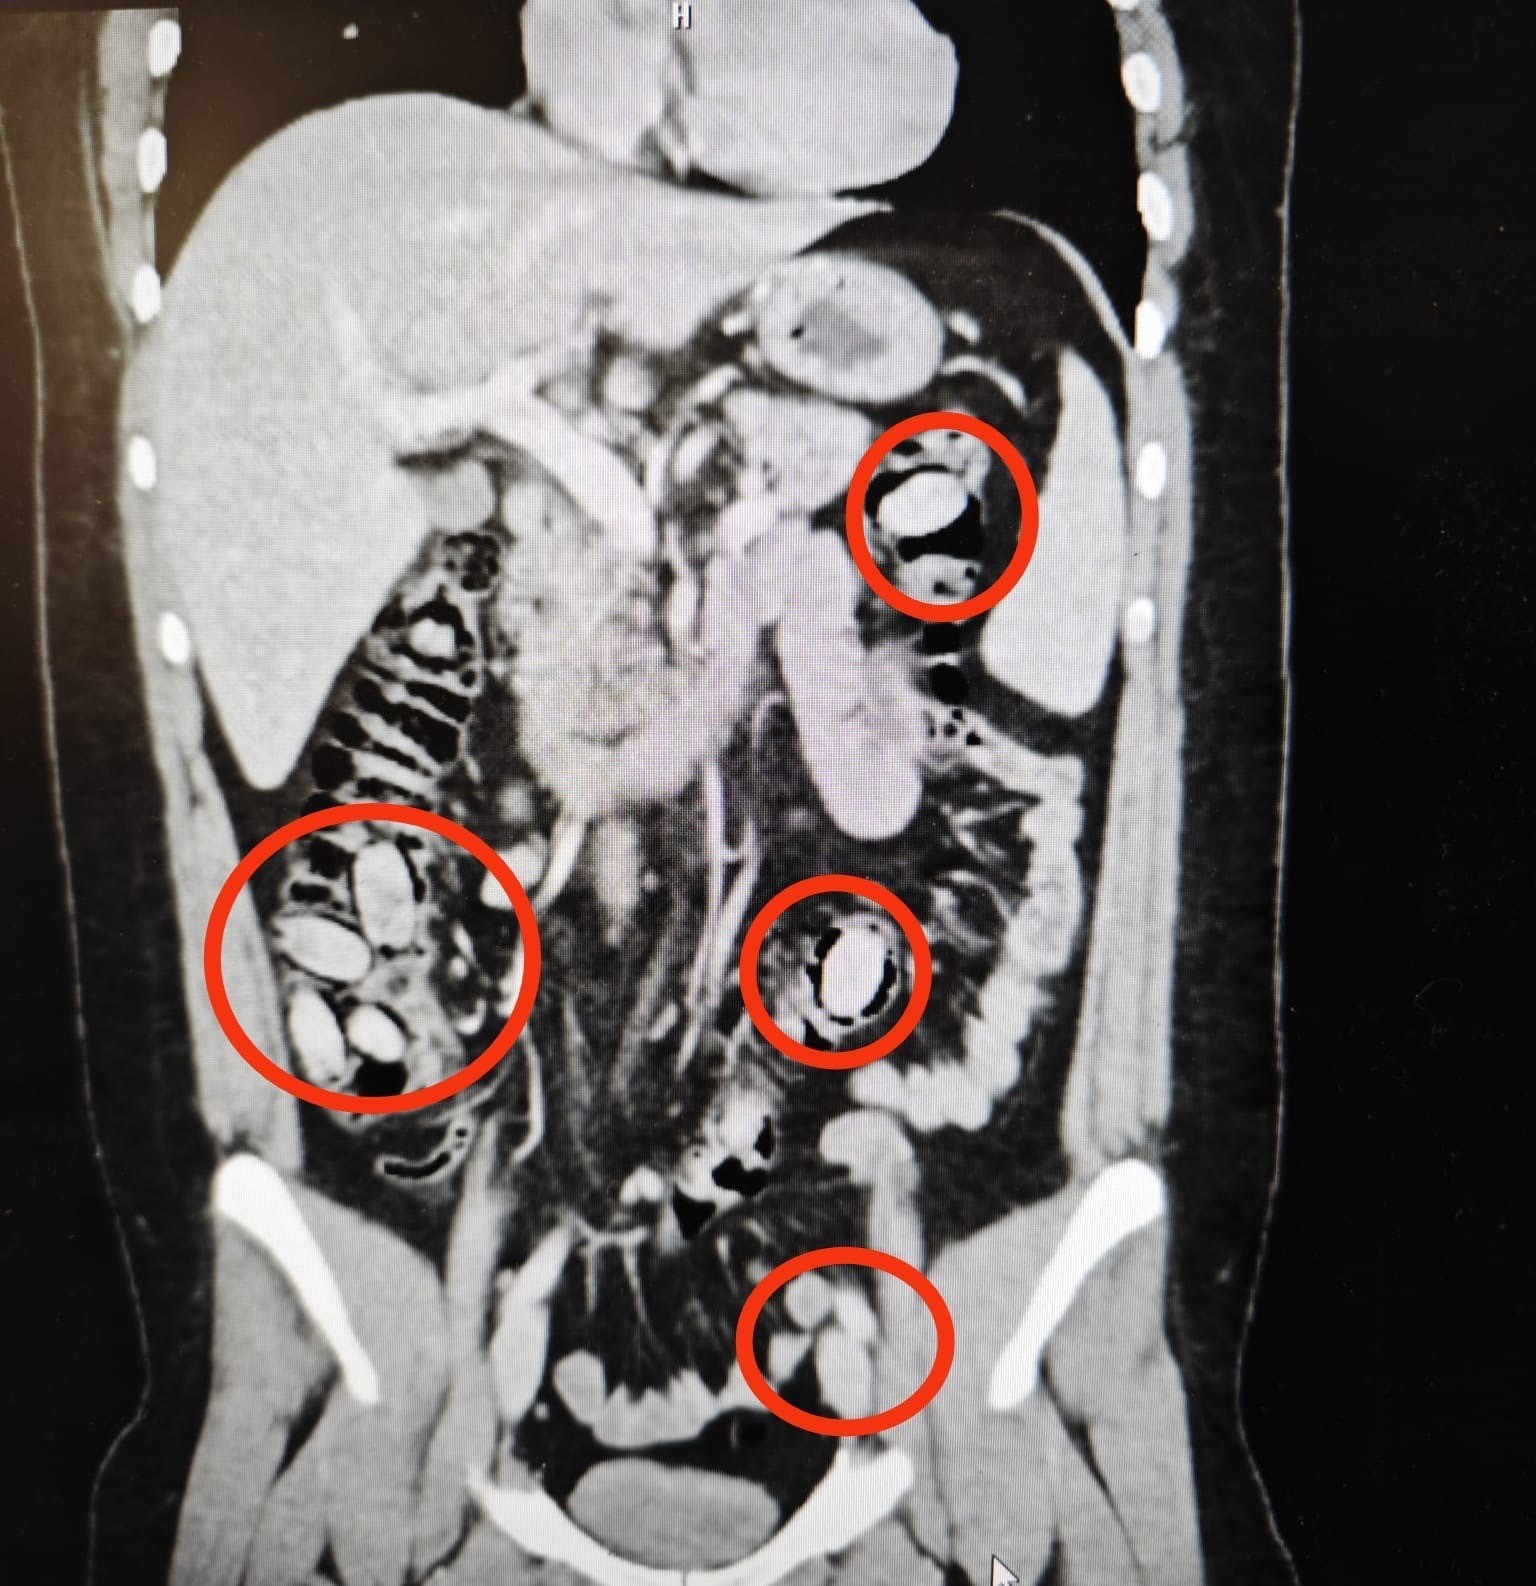

Yurtdışından Eskişehir’e gelen S.A. (25) isimli yabancı uyruklu şahsın kent girişindeki çevirme noktasında durumundan şüphelenilmesi üzerine hastanede yapılan detaylı tetkikler neticesinde yutmak suretiyle midesinde 44 kapsül metamfetamin maddesi taşıdığı anlaşıldı. Cerrahi müdahaleyle sözkonusu maddeler şahsın bedeninden çıkarıldı. Tedavisi akabinde şahıs tutuklandı. Yapılan titiz operasyon ile uyuşturucu maddelerin Eskişehir’de piyasaya sürülmeden ele geçirilmesi sağlandı.

Midesinde taşıdığı uyuşturucu maddeler polisin dikkatinden sayesinde ele geçirildi